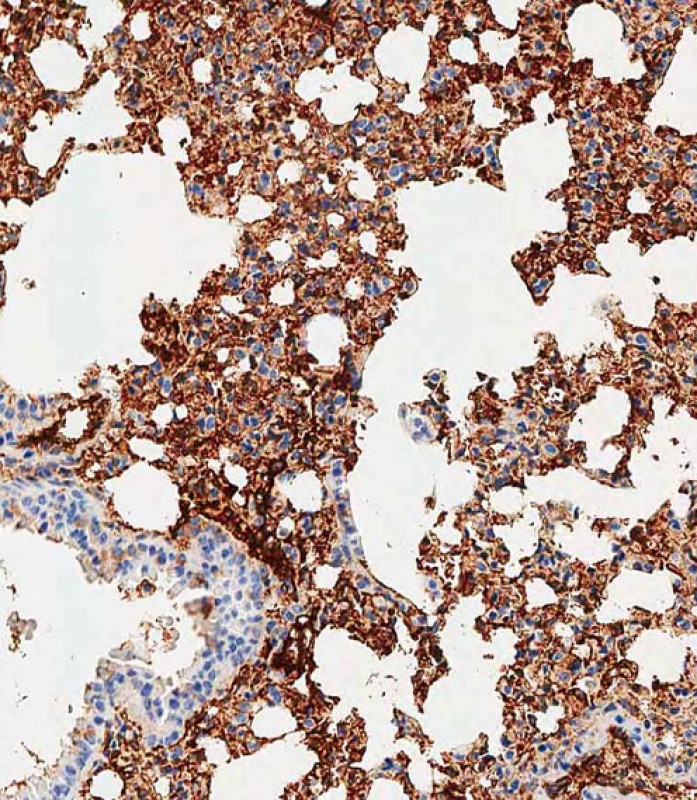

分类: 科研抗体货号: P34679别名: Macrophage colony-stimulating factor 1 receptor, CSF-1 receptor, CSF-1-R, CSF-1R, M-CSF-R, Proto-oncogene c-Fms, CD115, Csf1r, Csfmr, Fms应用: WB,IF反应种属: Mouse, Rat